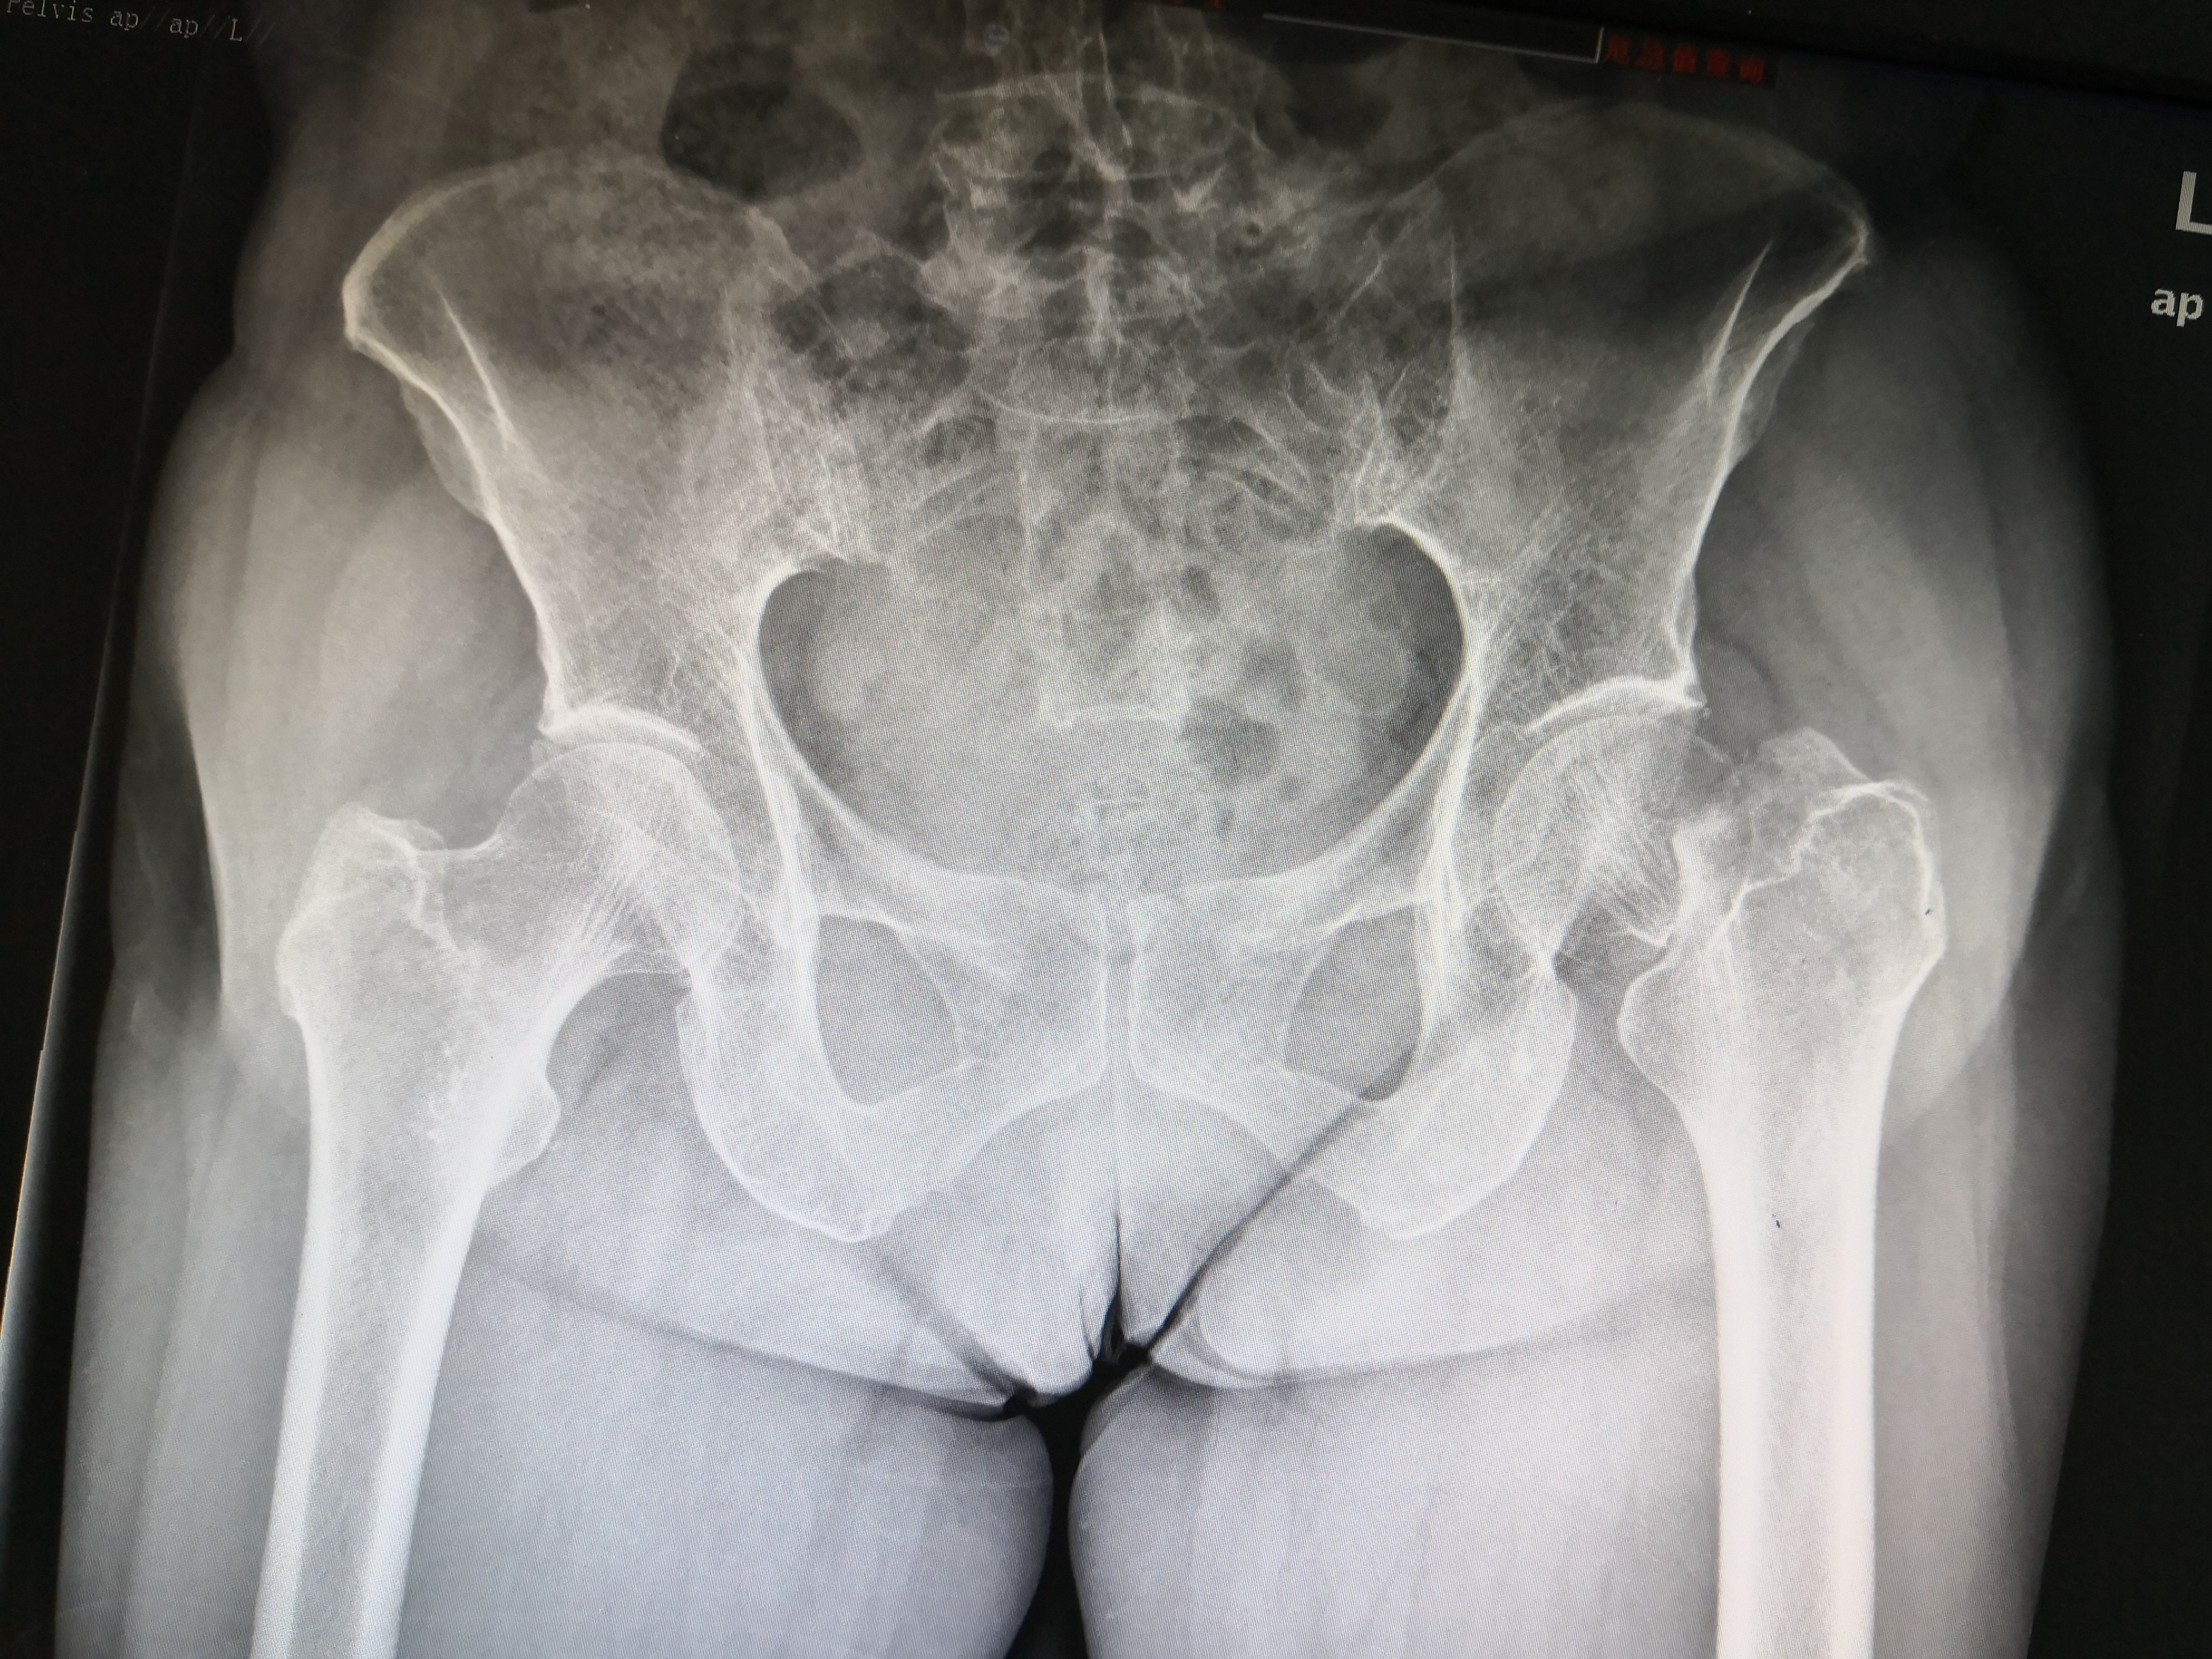

术前股骨颈骨折

IMG_20190323_185245.jpg